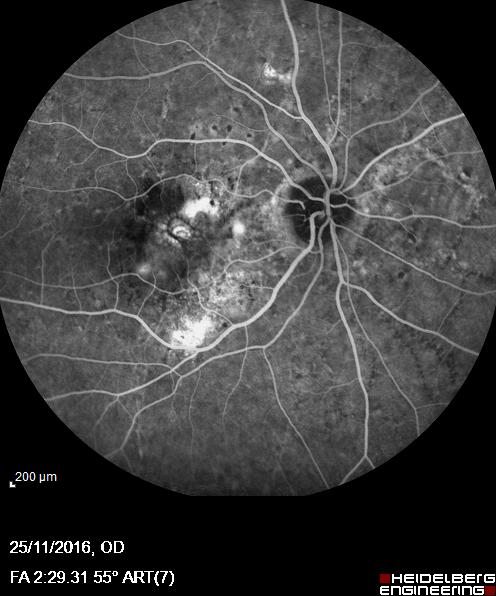

Oltre alle attività chirurgiche, il Dott. Acquaviva si avvale di tecnologie diagnostiche moderne per valutare in modo accurato lo stato di salute degli occhi. Esami come la tomografia a coerenza ottica (OCT), la pachimetria corneale e la misurazione del campo visivo sono strumenti fondamentali per un inquadramento completo e per la definizione del percorso terapeutico più efficace.